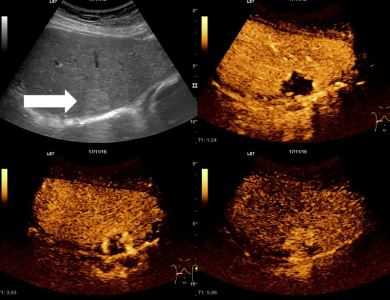

УЗИ печени при остром гепатите

При остром гепатите, без осложнений, клиническое выздоровление обычно наступает в течение 4 месяцев. Осложнения гепатит сопровождается повреждением печени и может варьироваться от легкого заболевания до массивных некрозов и печеночной недостаточности. На УЗИ печени врач может увидеть патологические изменения включают следующие:

Результаты ультразвукового исследования. На УЗИ текстура печени может казаться нормальной или сонографист может заметить, что границы воротной вены более заметным, чем обычно и паренхимы печени является немного более эхогенная, чем обычно, обогащение сосудистого рисунка зачастую присутствует. Определяется гепатоспленомегалия и утолщение стенки желчного пузыря.

Ультразвуковые признаки HBV

При гепатите В присутствует симптом диффузного снижения печеночной эхогенности. Чаще всего причиной гепатомегалии (увеличения органа) при данном заболевании, для которого характерное равномерное снижения эхогенности тканей печени, является острый гепатит.

Вследствие этих изменений стенки веток воротной вены выглядят более яркими - симптом «звездного неба». Довольно часто можно обнаружить утолщения стенок желчного пузыря. УЗИ не является основным методом диагностики при гепатите В и чаще всего используется для исключения других патологий печени.